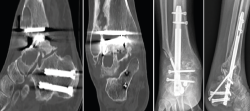

Figura 6. Imagen radiográfica y clínica en la que se aprecia la rotura parcial del clavo. Rescate con placa tibiotalar en proyección radiográfica en carga.

En este caso, la extracción fue sencilla: una vez retirados los tornillos de bloqueo, se realizó, con el sistema extractor del clavo, la extracción del mismo sin dificultad, ya que se trataba de una rotura incompleta. Realizamos un nuevo legrado de las superficies óseas, perforación de las mismas, nuevo aporte de injerto de cresta ilíaca y fijación con placa de artrodesis tibiotalar (Palex Medical), ya que la articulación subtalar estaba consolidada (Figura 6).